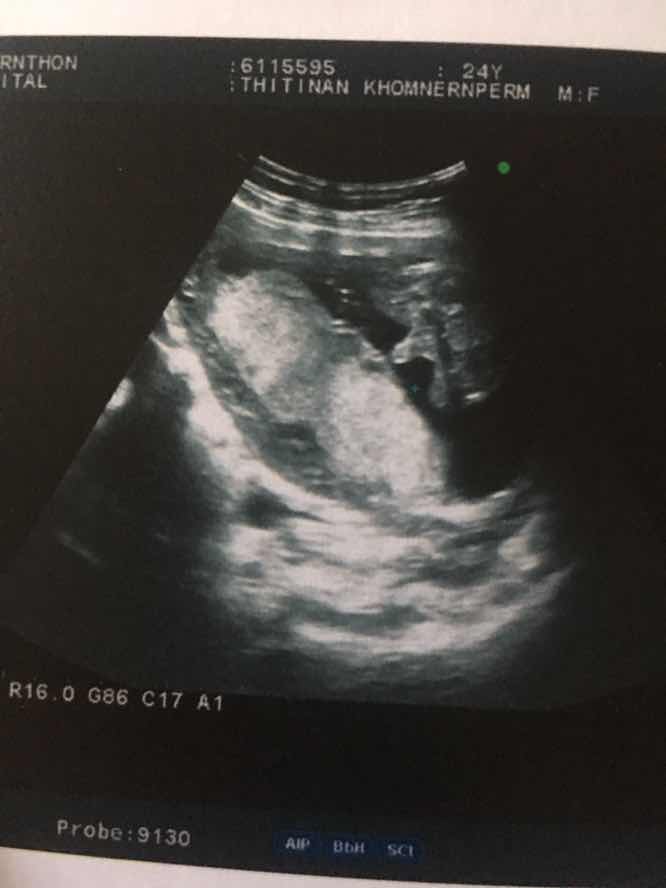

ขอดูใบซาวเด็ก ผช. ของแม่ๆ หน่อยค่ะ ?

ในภาพเป็น ผช ใช่ไหมค่ะ พอดีหมอขอชัวร์ๆ เดือนหน้า เลยสอบถามแม่ๆ ที่มีประสบการณ์ลูกชาย หน่อยค่ะ ?ขอดูใบอัตตลาซาวเด็ก ผช . หน่อยจร้าาา? ถาพไม่ชัดเพราะถ่าย VDO มาจร้า ??

ผช คะ